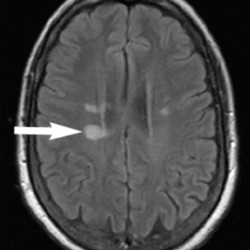

- MRI imaging with contrast is the most important imaging modality in the workup of possible MS.

- Demyelinating lesions related to MS are ovoid, >3 mm in diameter, and are typically located in particular regions: periventricular (Dawson’s fingers), juxtacortical, cortical, or spinal cord.